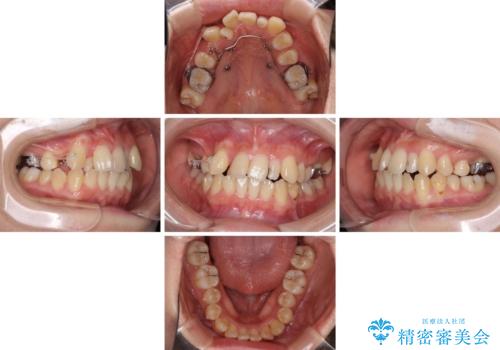

八重歯の抜歯矯正 補助装置を用いたインビザライン矯正

- 上顎の重なっている前歯を気にして来院された患者様です。

重なっている部分は抜歯が必要で、歯の移動量が多く、更には右側にずれている正中を改善する必要がありました。

インビザライン単体での治療は困難と判断し、補助装置により八重歯移動後にインビザラインを用いることとしました。

非常にしっかりとマウスピースを装着してくださいましたが、前歯の排列がなかなか仕上がらずに期間がかかってしまいました。